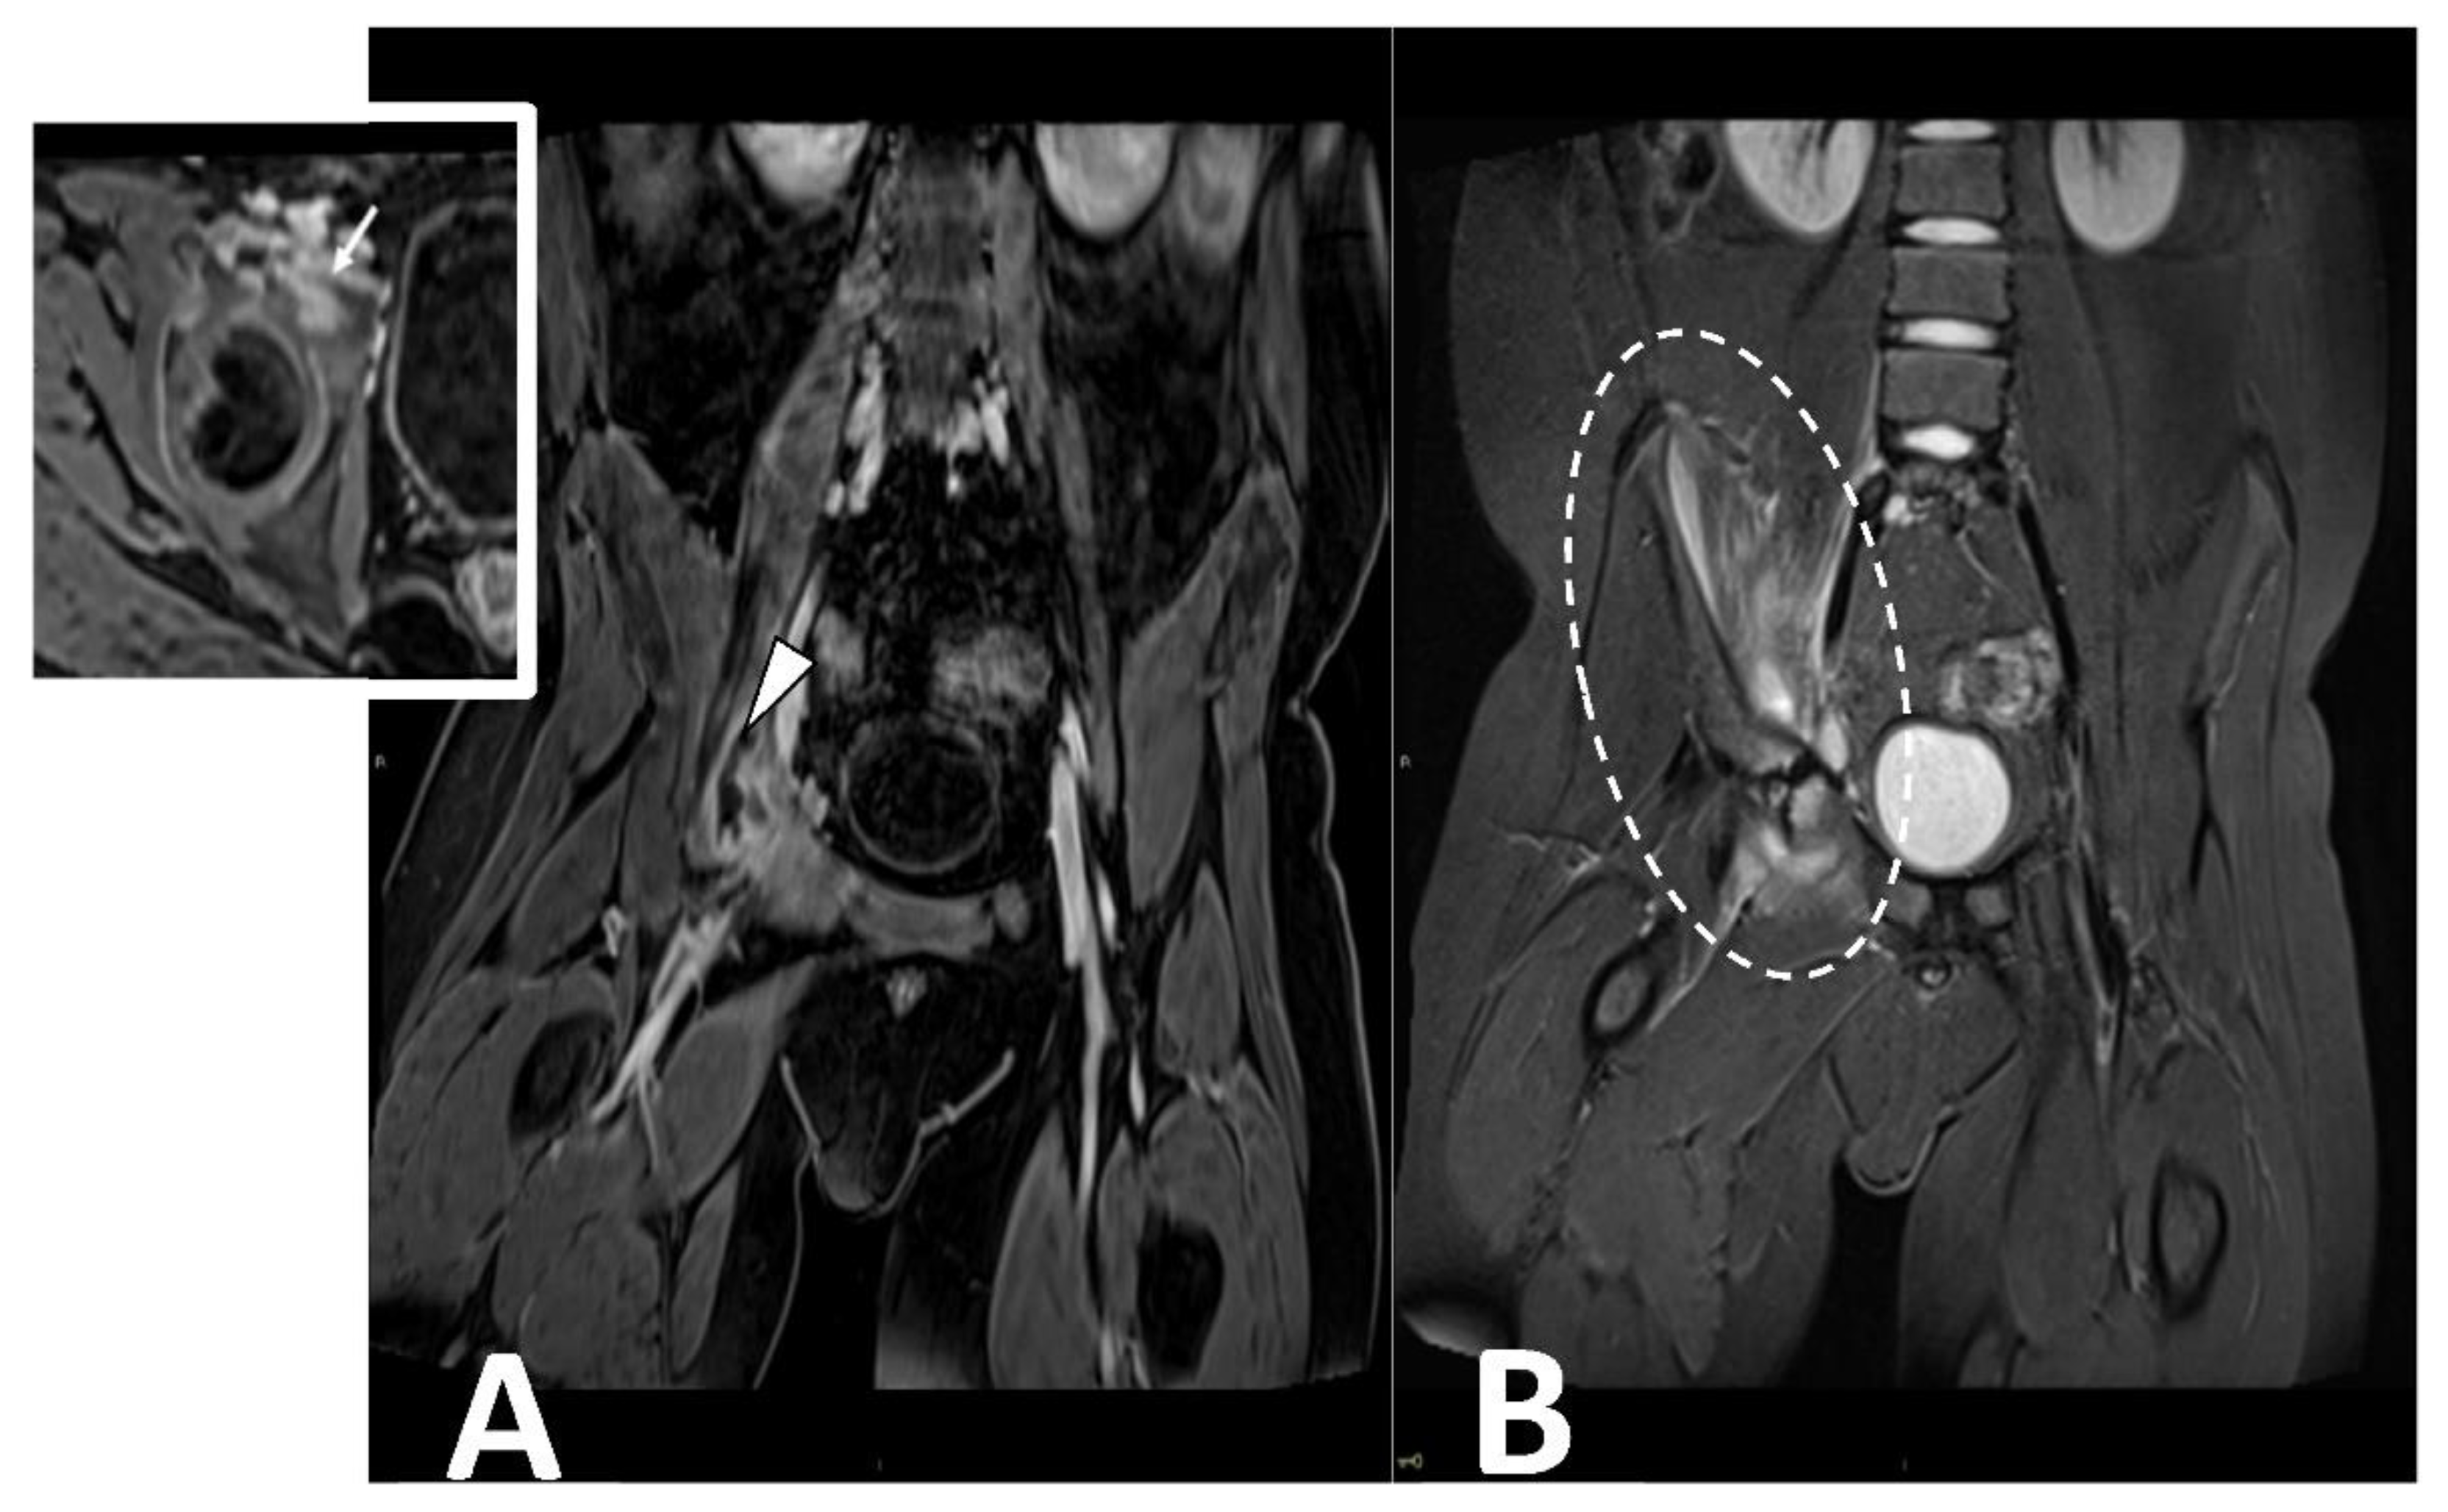

2.5. Infectious Myositis